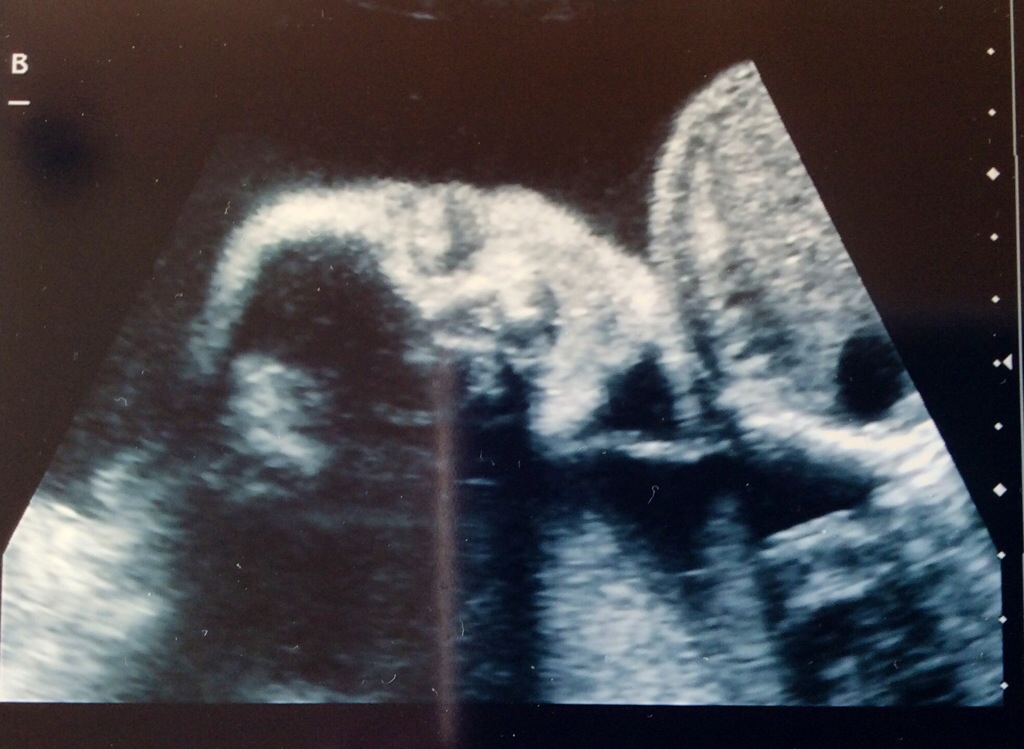

Monday we had our fetal echo and it looks like both babies hearts are just fine. Sigh of relief! Baby A still has her small calcification, but the radiologist was not concerned at all and said not to worry. We also had another growth check at this same ultrasound appointment. Baby A is estimated to be 1 lb 14 oz and Baby B is estimated to be 2 lbs. Baby A is in the 67th percentile and Baby B is in the 83rd percentile. They are growing and we couldn’t be happier!

Baby B Frontal View #2